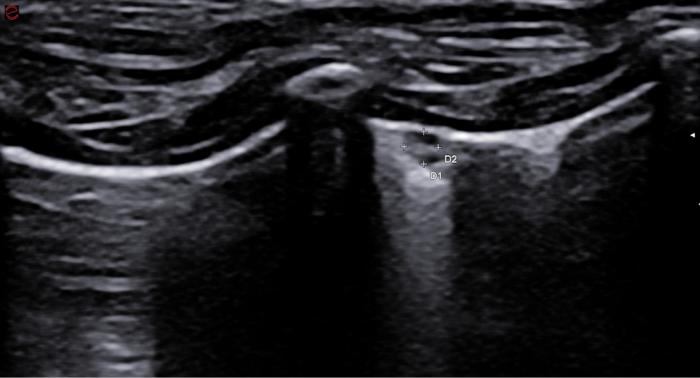

Signo nodular

Consiste en una consolidación de aspecto circular a menudo de anecoicos a hipoecoicos con rara aparición de broncogramas en su interior. Distalmente al signo nodular observamos una línea cóncava hiperecogénica llamada línea C y un refuerzo posterior o signo de brillo en la profundidad del campo. Este hallazgo es común en neoplasias primarias o metastásicas, granulomas fúngicos o abscesos. Es un signo de especial importancia cuando tenemos un paciente con historial oncológico previo o en el protocolo de búsqueda de metástasis. Los nódulos observados veremos cómo se desplazan de izquierda a derecha de la imagen con la respiración del paciente, haciendo patente que se encuentran a nivel pulmonar y no de la pared costal, en cuyo caso no se desplazaran mientras el transductor se encuentre inmóvil (Figura 16A-D).